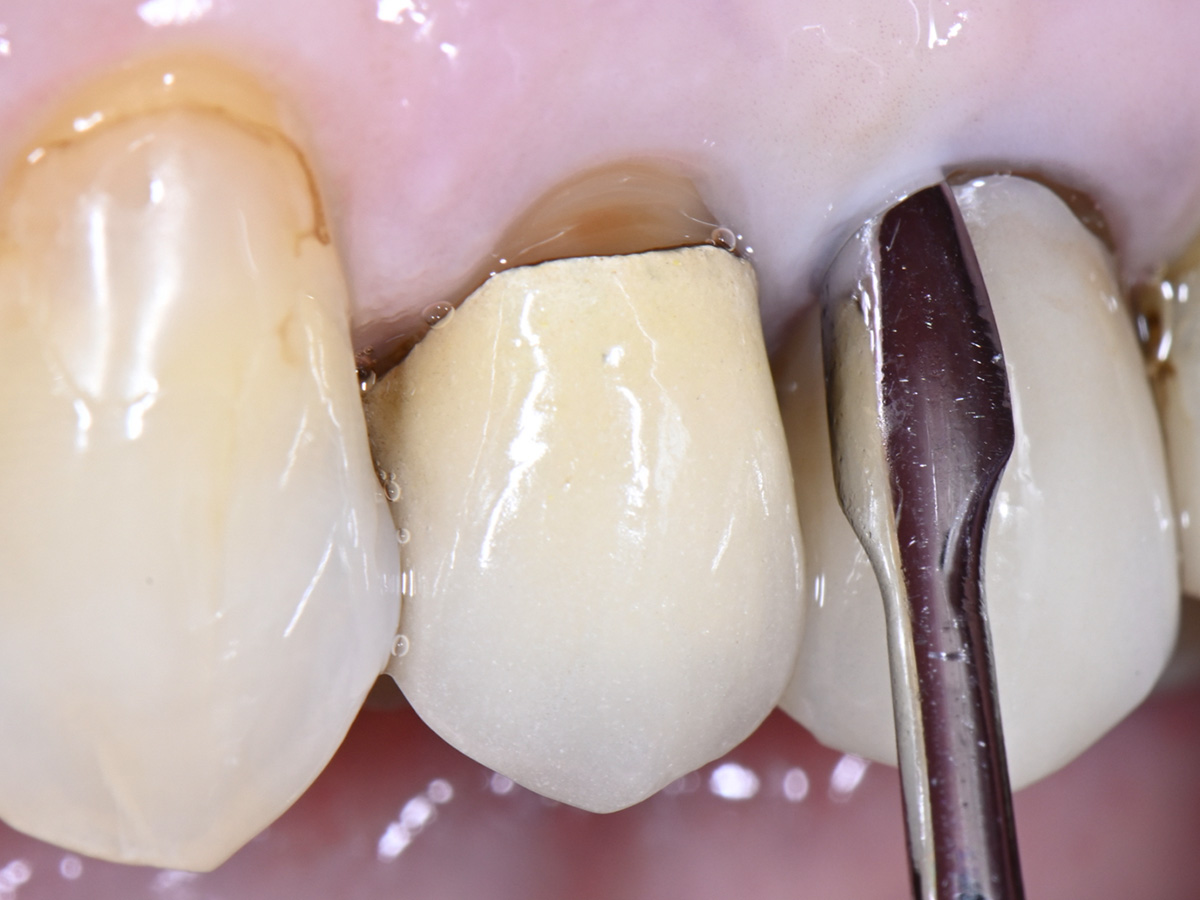

Abbildung 15

Eine individuelle Heilungskappe wird am Ende auf das Implantat aufgeschraubt

Abbildung 16

Klinisches Abschlussbild nach Einsetzen einer verschraubten Implantatkrone